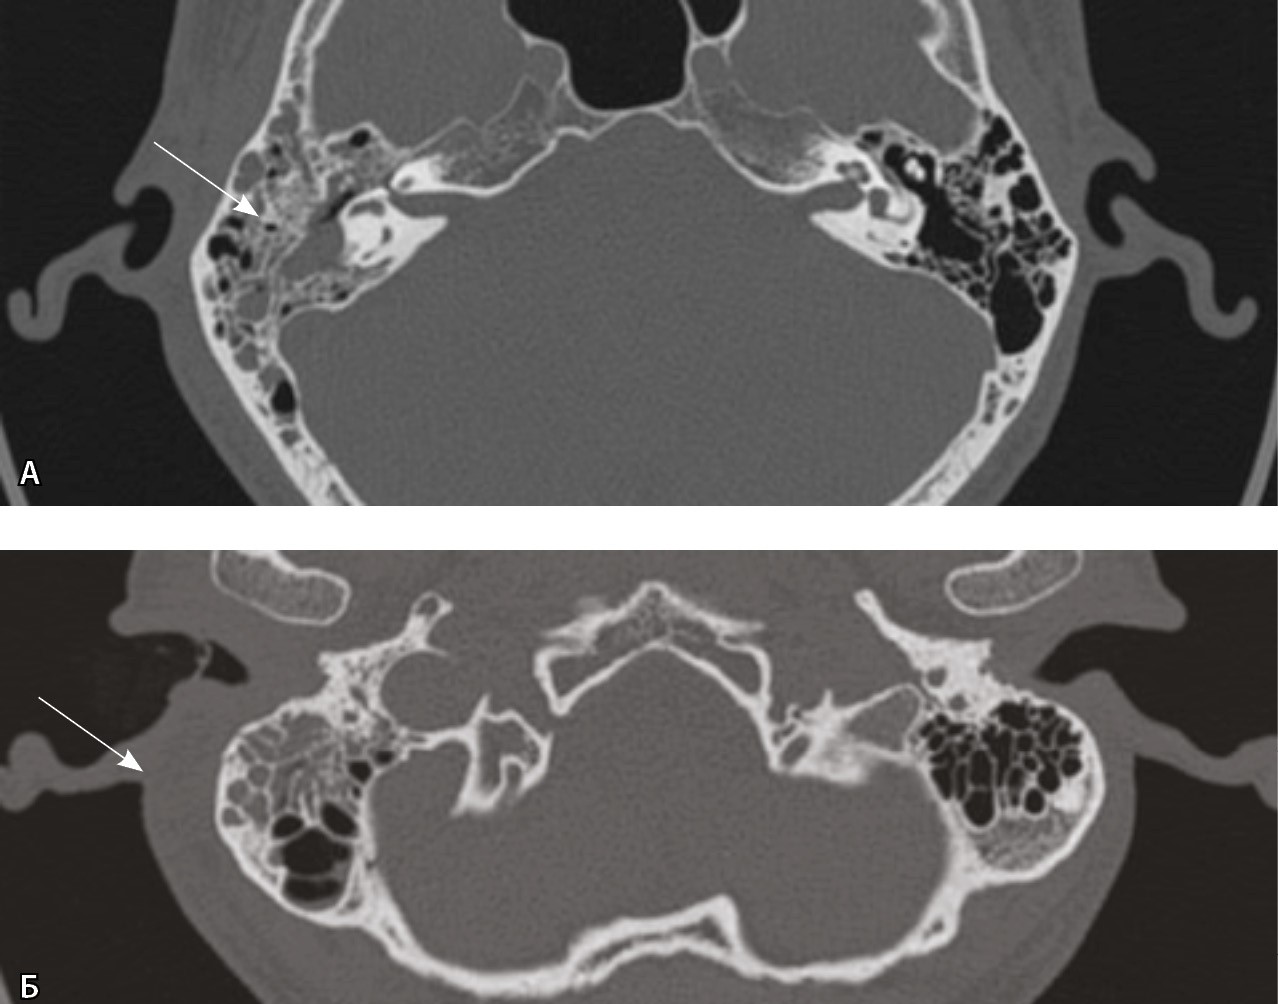

Выполнена КТ височных костей, а затем КТ шеи с контрастом. При КТ височной кости справа определялся пневматического типа строения сосцевидный отросток, практически все ячейки которого были выполнены субстратом. При этом деструктивных изменений как костных стенок ячеек, так и кортикального слоя достоверно не определено (рис. 2).

Рис. 2. Компьютерная томография височной кости, аксиальный скан, костное окно. А – в клетках сосцевидного отростка, антруме и барабанной полости справа определяется содержимое (стрелка); Б – асимметричное утолщение парааурикулярных мягких тканей справа (стрелка)